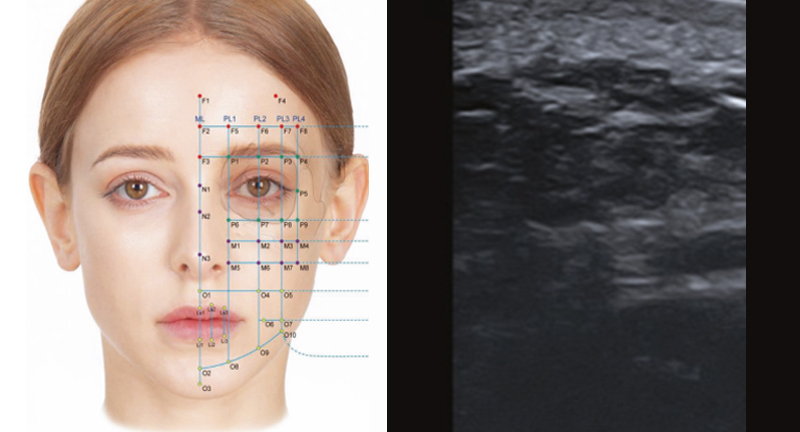

객관적인 안면 내부의 평가를 원하며 이를 통한 교정을 받고 싶은 분

초음파의학회 정회원 전문의의 전문적인 안면초음파로 내부 볼륨 문제의 확인이 가능하며 개선 또한 가능합니다

필요시 얼굴 초음파를 포함, 피부층의 분석, 리니어 캐뉼라 테크닉을 바탕으로 개개인마다 가장 최적화된 깊이, 분포, 용량을 정밀 조정합니다.

얼굴의 내면부의 볼륨의 꺼짐은 개인별로 원인에 큰 차이가 있을수 있습니다.

저희 의원은 필요시 안면의 해당 부분에 대한 초음파를 통한 내부의 상세한 분석이 가능하며

단순한 채움의 시술이 아닌 명확한 원인의 판단과 정확한 시술이 가능합니다.

단순한 ‘채움이 아닌’ 필요시 안면 초음파를 기반, 정밀성에 근거한 시술이 진행될수 있습니다.

• - 얼굴의 해부학적 구조를 실시간으로 확인할 수 있는 초음파 진단기기와 상세한 진료

• - 안전하게, 필요한 부위에 대한 정확한 시술